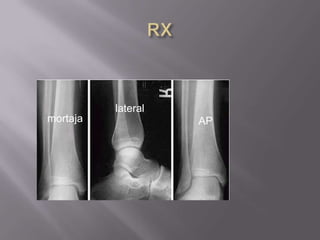

EvaluaciónClinicaHistoriaExamen físicoRXAPLateralMortaja

RXlateralmortajaAP